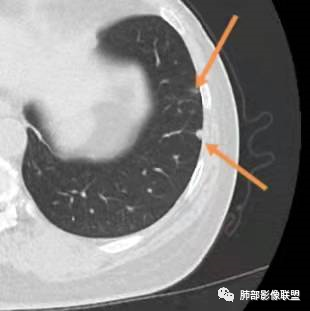

影像特点:右肺上叶混合磨玻璃影,边界清晰,结构松散,内有多结节堆积及支气管扩张影,可见小叶间隔增厚,并局部增厚的小叶间隔上亦存在微结节,胸膜侧可见纤细索条,病灶周围可见多发微结节影。

总体分析:从病灶分布来看符合结核的好发位置,影像表现也符合结核的多态性,且出现卫星灶。由于有边界清晰的GGO,需要鉴别腺癌,虽然此病例有边界清晰的GGO,但是它的GGO的边缘有结节感,呈多结节堆积,而腺癌的GGO缺乏这种“多结节堆积感”,另外,此病例也没有发现腺癌的胸膜凹陷征、毛刺征及月牙铲等。